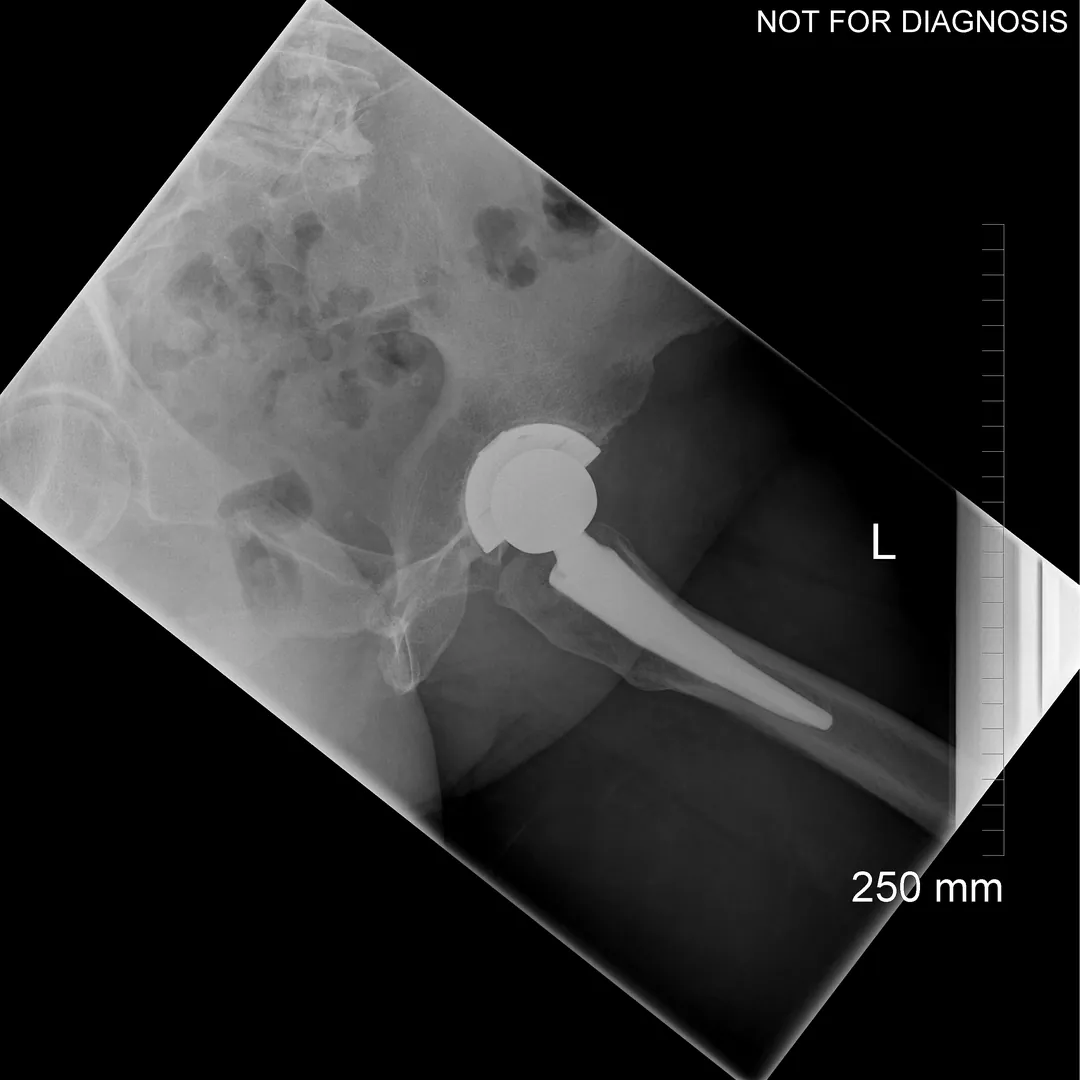

A total hip replacement (also called total hip arthroplasty) is a surgical procedure in which a damaged or worn hip joint is replaced with artificial components. The hip is a ball-and-socket joint, meaning the ball at the top of the thigh bone sits in a socket on the pelvis. During surgery, the damaged ball (femoral head) is replaced with a metal or ceramic ball attached to a stem, and the damaged socket is replaced with a metal cup lined with plastic, ceramic, or metal.

- The surgeon removes the damaged bone and cartilage and inserts the artificial joint